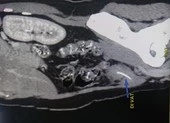

Tại Bệnh viện Đa khoa Trung ương Cần Thơ, sau khi chụp cắt lớp vi tính hệ tiết niệu, các bác sĩ xác định trong cơ thể cụ bà còn ống thông bị đứt đoạn ở vị trí  bàng quang tạo thành sỏi to. Phần đầu trên ống có sỏi nhỏ bám.

Các bác sĩ đã phẫu thuật lấy thành công viên sỏi bàng quang lớn bằng quả trứng, kích thước 5 x 4 x 5 cm có đầu ống thông bên trong, đồng thời rút thành công ống thông.